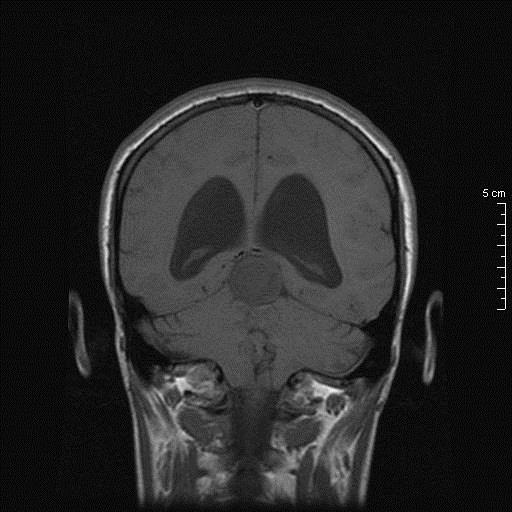

Γυναίκα 34 ετών παρουσιάστηκε με κεφαλαλγία, περιστασιακά διπλωπία και στην εξέταση οίδημα οπτικών θηλών. Η μαγνητική τομογραφία κατέδειξε βλάβη διαμέτρου 26.7 χιλ στην περιοχή της επίφυσης χωρίς ενίσχυση, με πίεση επί του τετραδύμου και σημαντική διάταση του κοιλιακού συστήματος. Σε θέση park bench υποβλήθηκε σε δεξιά πλάγια περιορισμένη ινιακή κρανιοτομία και μέσω της υποσκηνίδιας υπερπαρεγκεφαλιδικής οδού σε ενδοσκοπικά υποβοηθούμενη μακροσκοπικά πλήρη αφαίρεση της βλάβης.

Προεγχειρητικός απεικονιστικός έλεγχος